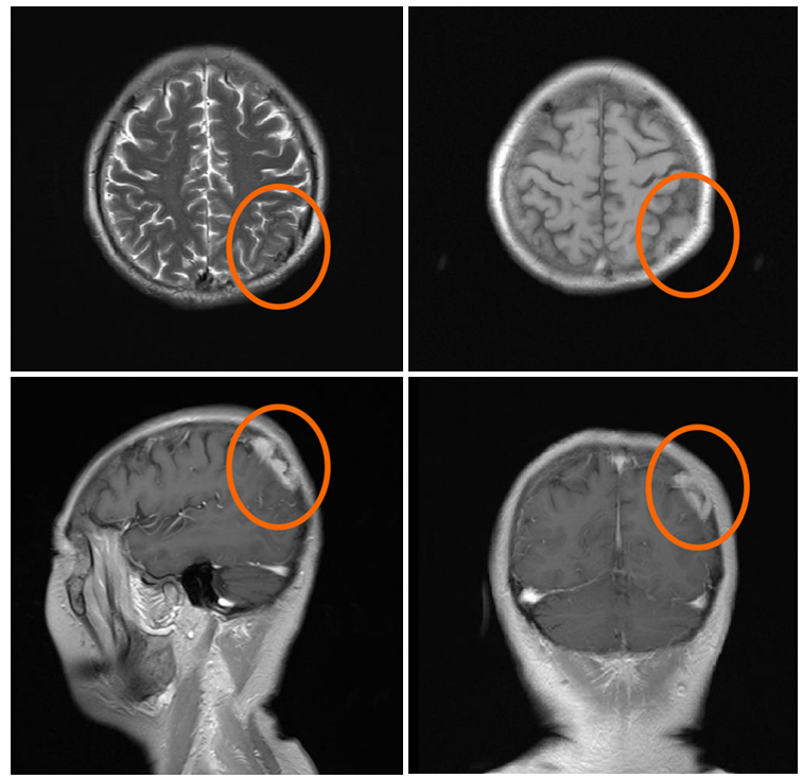

脑部 MRI 显示右侧顶骨溶骨性破坏(骨转移);

脑部磁共振成像显示吉非替尼治疗后肿瘤的进展情况。红色圆圈所示为溶骨性骨病变